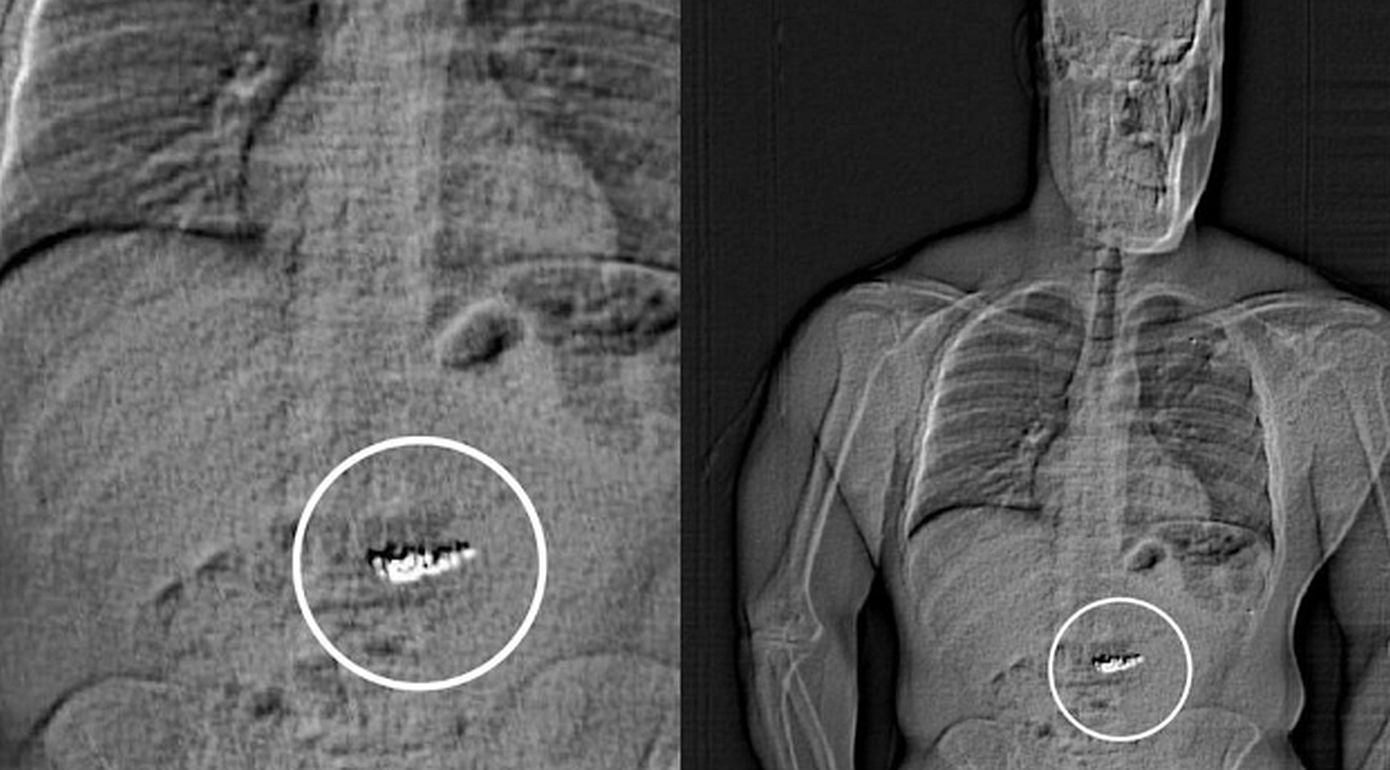

Η αστυνομία εξέτασε το βίντεο παρακολούθησης στο εμπορικό κέντρο και εντόπισε τον 32χρονο να κατευθυνόταν προς το Τέξας. Αμέσως σήμανε συναγερμός και τον συνέλαβαν. Στη συνέχεια έγινε ακτινογραφία όπου διαπιστώθηκε ότι τα κοσμήματα βρίσκονταν στο στομάχι του.

Ο 32χρονος μεταφέρθηκε στο νοσοκομείο όπου νοσηλεύτηκε φρουρούμενος μέχρι να αποβάλλει με φυσικό τρόπο τα διαμάντια.

Σύμφωνα με την αστυνομία αρχικά «ανακτήθηκαν» 3 από τα 4 σκουλαρίκια και δύο ημέρες αργότερα στις 12 Μαρτίου το τελευταίο κομμάτι.